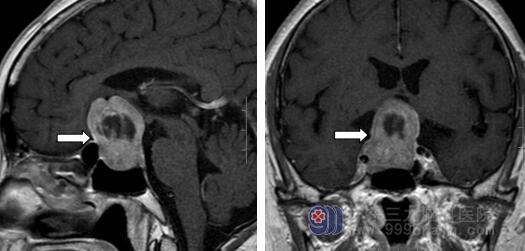

住院后安排于奶奶进行详细的检查,行内分泌检验、视力及视野检查、垂体MR平扫+增强检查,磁共振报告结果提示:鞍内及鞍上区占位性病变,大小约27*27*37mm,增强后不均匀强化,包绕邻近右侧颈内动脉及海绵窦,视交叉及垂体柄受压。

从影像学资料上看,患者的瘤体较大,占据鞍区,视交叉及垂体柄受压,应施行手术切除,解除压迫。神经外十科组织科室讨论,决定采用神经内镜经鼻蝶入路微创手术治疗。术前,护理人员积极为于奶奶进行肺呼吸锻炼的健康宣教,希望为其术后快速康复做好铺垫。